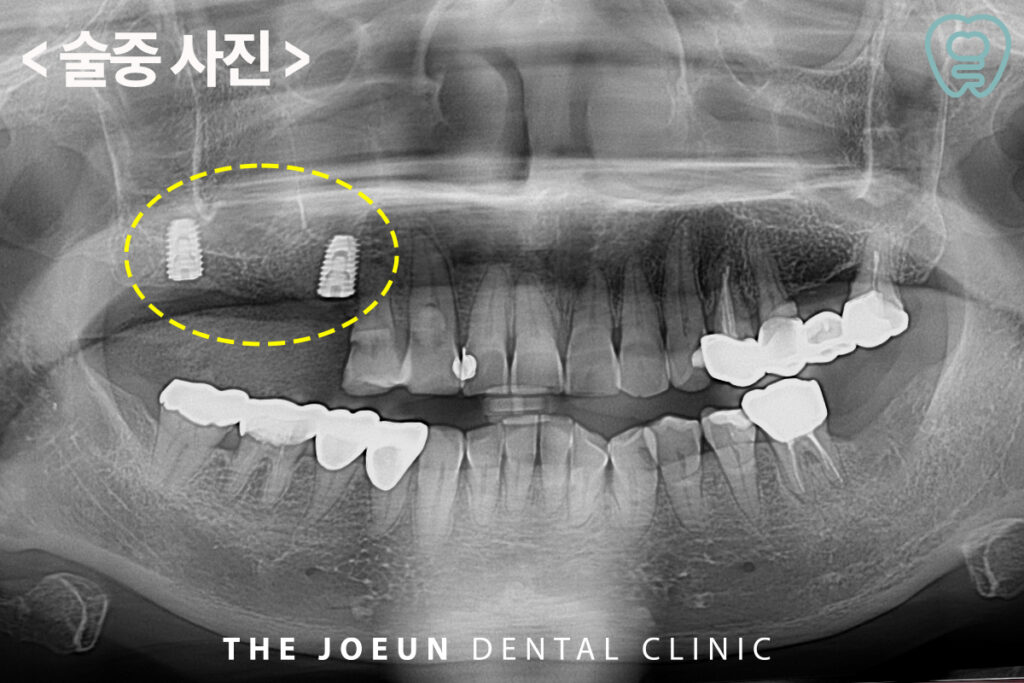

당일 바로 상악동 거상술과 임플란트 식립을 진행하였는데요. 치조정 접근을 통한 상악동 거상술을 함께 진행하였습니다.

이 방법은 남은뼈가 3mm 이상인 경우 상악동을 상방으로 거상시키면서 골이식과 임플란트 식립을 동시에 진행할 수 있는 방법을 말하는데요. 수술 시간이 길지 않고 수술 후 붓기와 통증이 상대적으로 적다는 장점이 있습니다. 또한, 환자분들의 수술 후 불편감을 줄여드릴 수 있으며 부작용 및 통증도 줄일 수 있습니다.